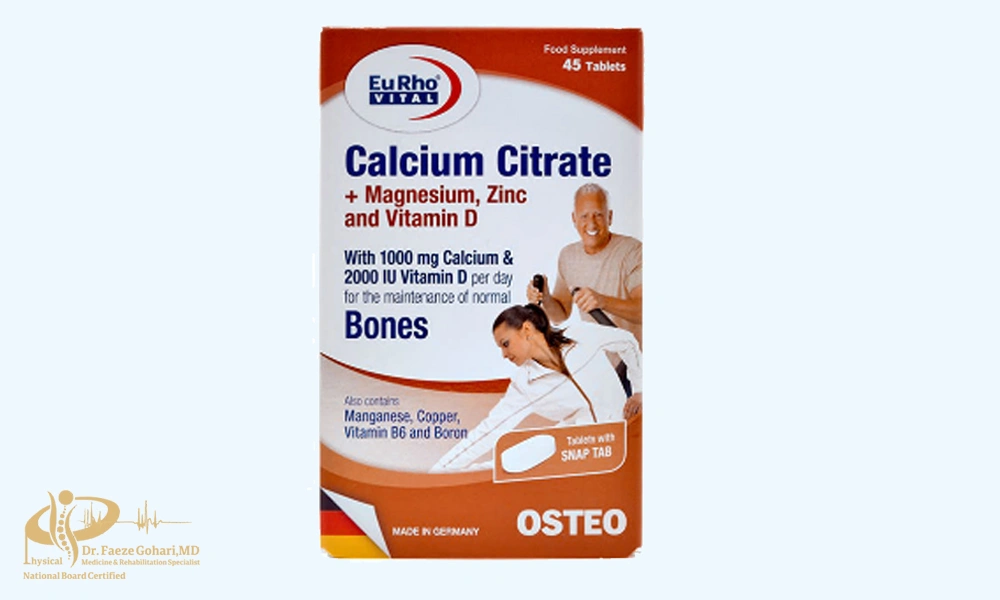

| آرتروستاپ رپید: گلوکزامین، کندرویتین، MSM، کلاژن، ویتامین C استئو بایفلکس: گلوکزامین، کندرویتین، MSM، هیالورونیک اسید جوینتایس: گلوکزامین، کندرویتین، MSM، ویتامین D، زینک آرترو اید: گلوکزامین سولفات، MSM موو فری ادونسد: گلوکزامین، کندرویتین، کلاژن نوع ۲، هیالورونیک اسید فلکس موو پلاس: گلوکزامین، کندرویتین، MSM، زینک، ویتامین D3 آرتروژل: گلوکزامین سولفات، کندرویتین، MSM آرتریکس: گلوکزامین، کندرویتین، MSM، ویتامین D3، زینک آرتروپرو: گلوکزامین سولفات، کلاژن، هیالورونیک اسید آروما ویتا فلکس: گلوکزامین، کندرویتین، MSM، کورکومین ASU (آووکادو سویا غیرصابونی): 300 میلیگرم ASU پایه روزانه ساپلاس مدز (در دست بررسی): گلوکزامین، کندرویتین، MSM یوروویتال (در دست بررسی): گلوکزامین، کندرویتین، ویتامین D نیوویتال (در دست بررسی): گلوکزامین، کندرویتین، مواد معدنی آرتمیس (در دست بررسی): گلوکزامین، کندرویتین، MSM |

| استئو بایفلکس، موو فری ادونسد: آمریکا آرترو اید: استرالیا جوینتایس: انگلستان آرتروستاپ رپید: جمهوری چک فلکس موو پلاس، آرتروژل، آرتریکس، آروما ویتا فلکس، ساپلاس مدز، نیوویتال، آرتمیس: ایران آرتروپرو: ایران (تحت لیسانس) ASU: فرانسه/ ایتالیا یا تحت لیسانس |